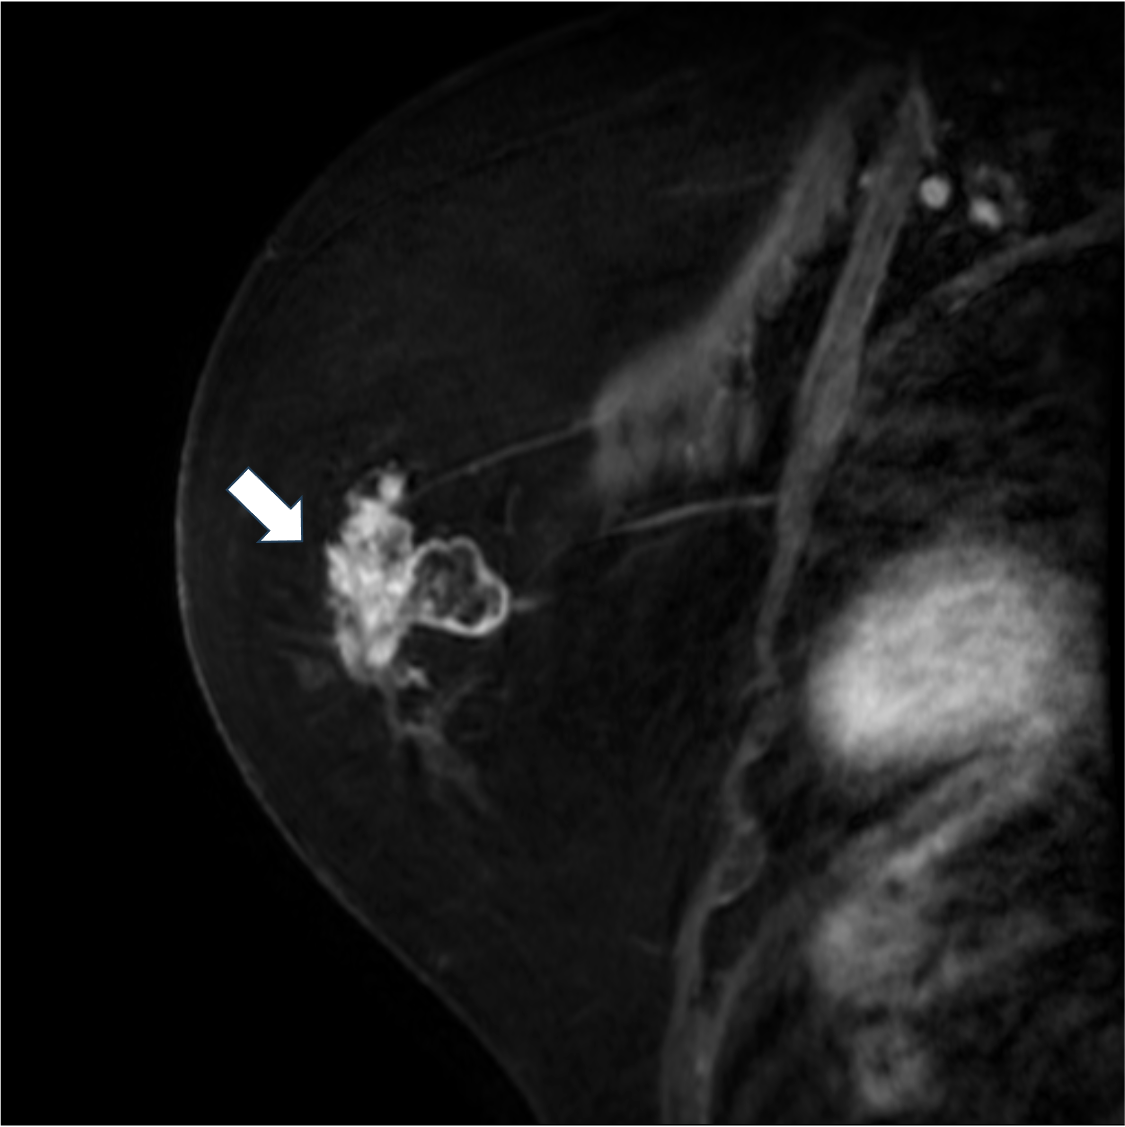

7. 造影後高分解能T1強調画像

造影後高分解能T1強調画像は不整な腫瘤の形状や不均一な内部構造が明瞭に描出されている。乳頭側に強い造影効果がある豊富な充実成分の存在が示唆される。